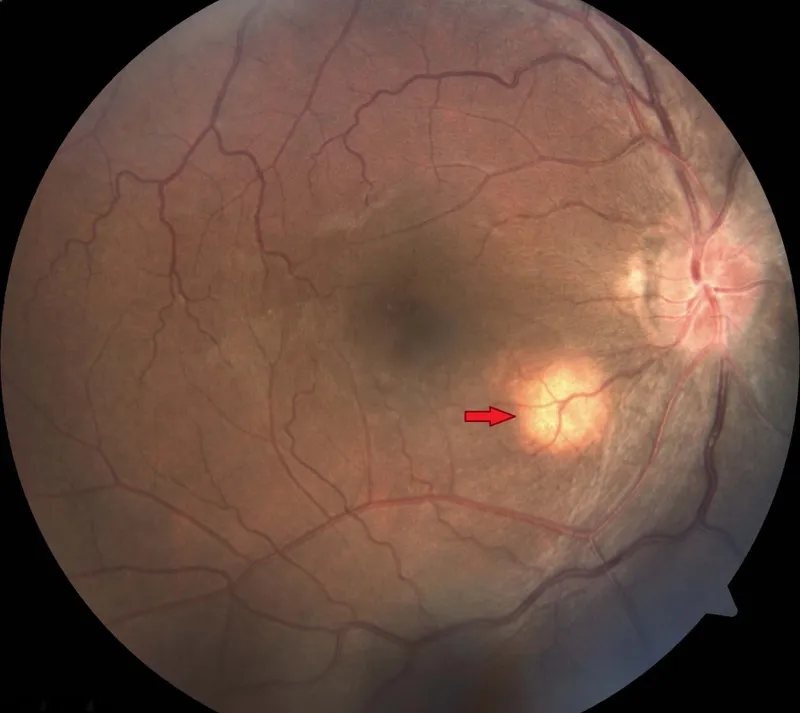

- Fundoscopy: Choroidal tubercles.

⭐ Choroidal tubercles on fundoscopy are pathognomonic for miliary TB.